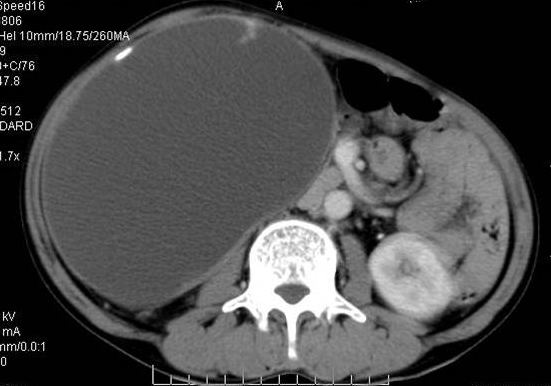

男性 60岁,腹部肿块4年余,肿块逐渐增大,活动性差,无血尿。

ct值测量

右肾脏巨大囊样影、囊壁有钙化,囊样影轻度强化有软组织成份。不除外畸胎瘤可能。

巨大囊性肿块,囊壁较厚有强化,有团片状钙化,病灶内下方灶内见片絮状高密度影,增强有轻中度强化,考虑囊性肾癌可能性大

定性;病灶囊性为主,前下部含实性成分,及钙化,部分壁厚薄不均。

可考虑 1畸胎瘤 2肾包囊虫 3囊性肾瘤或囊性肾癌 4重复肾伴积水。